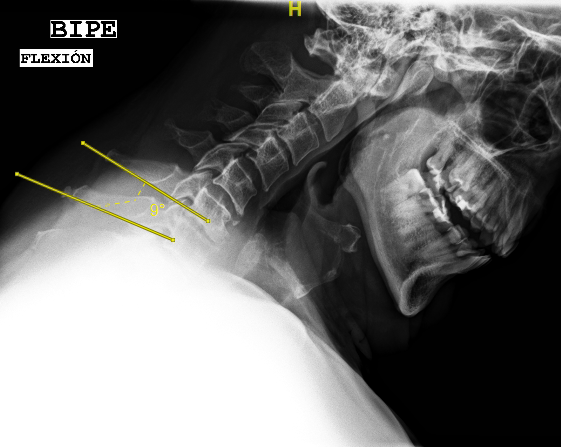

Las RX dinámicas reflejan la ausencia de fusión C6-C7